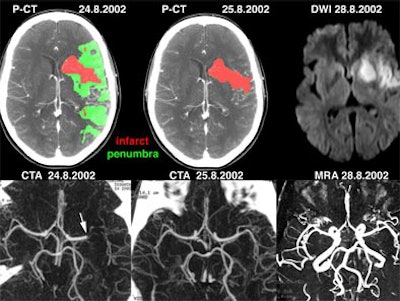

![]() |

| Recent CT survey of a 62-year-old male patient admitted to our emergency room with a) left hemisyndrome, including a) perfusion CT and b-e) CT angiography (CTA). Above: From the perfusion CT raw data (first line), three parametric maps can be extracted relating to mean transit time (MTT, second line), regional cerebral blood flow (rCBF, third line) and regional cerebral blood volume (rCBV, fourth line), respectively. Applying the concept of cerebral vascular autoregulation leads to a prognostic map (fifth line), describing the infarct in red and the penumbra in green, the latter being the target of thrombolytic drugs. Below: b, c) CTA enables identification of the origin of the hemodynamic disturbance demonstrated by perfusion CT. In this patient, it relates to an occlusion at the right M1-M2 junction (arrows). d, e) Finally, CTA features bilateral calcified atheromatous plaques at both carotid bifurcations (arrowheads). Images courtesy of Dr. Max Wintermark. |